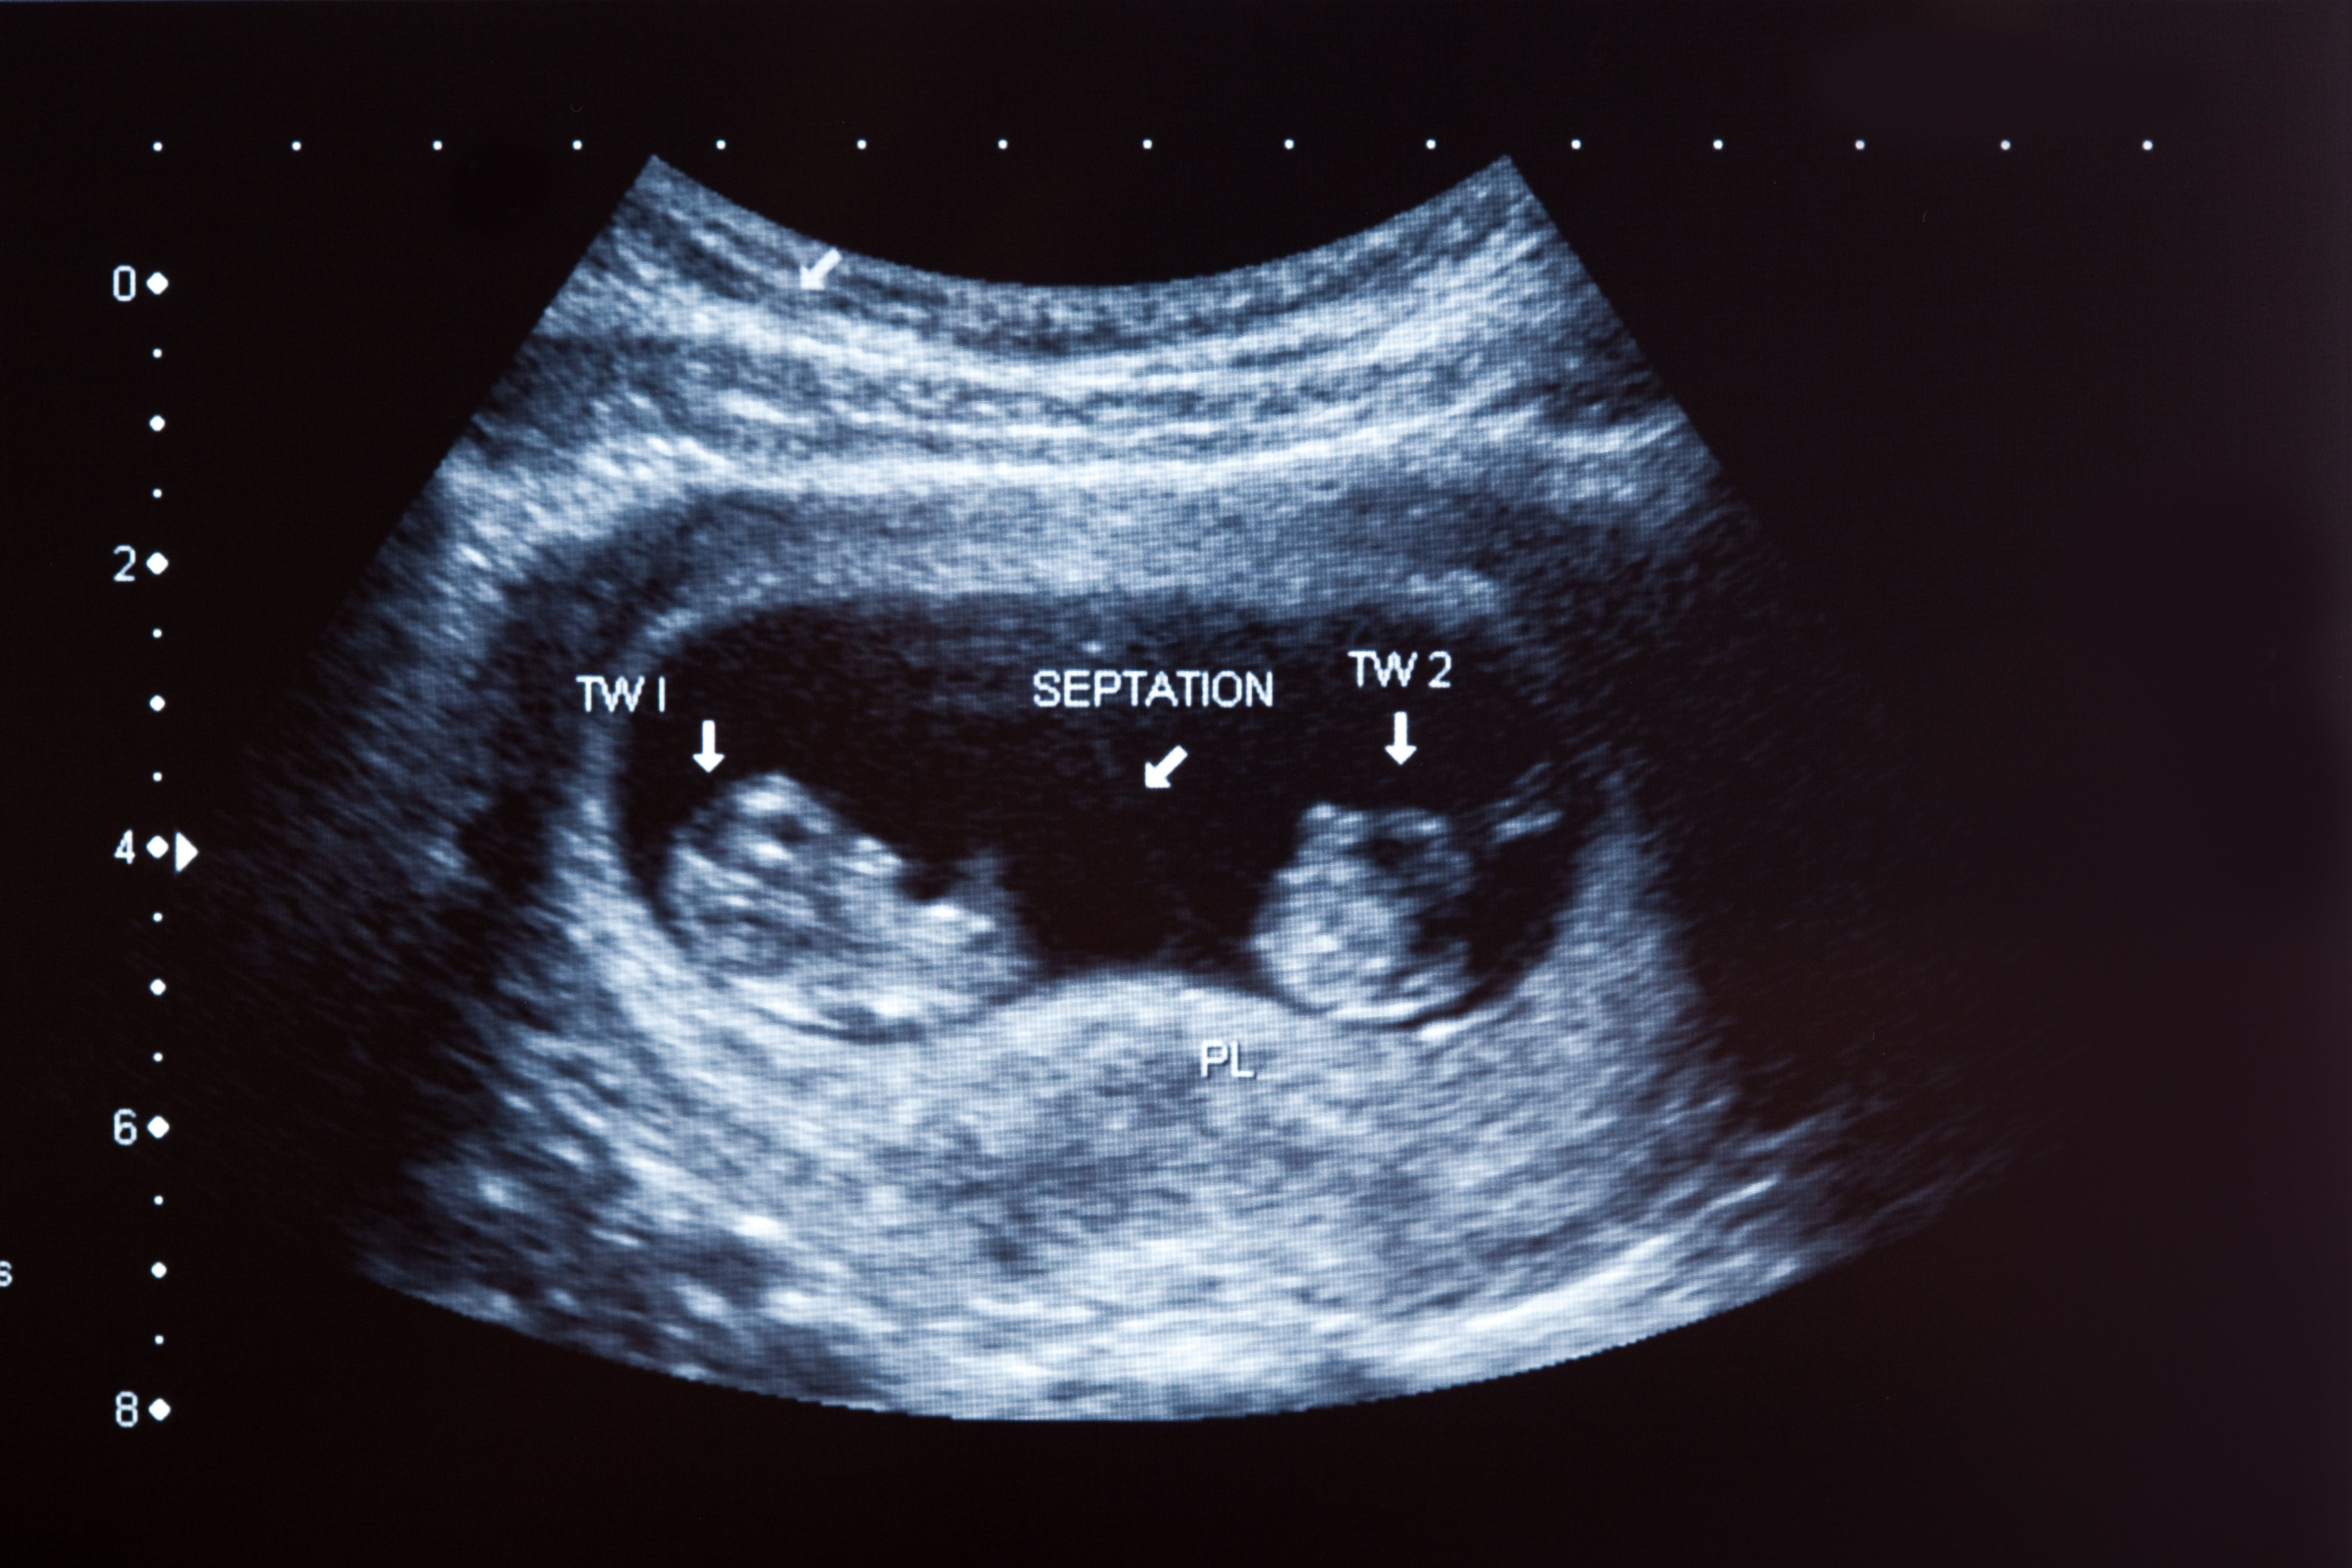

Only dichorionic twin pregnancies were included in the twin pregnancy cohort, determined by the presence of 2 gestational sacs with a thick intervening membrane. First-trimester ultrasonography was used to determine participants’ menstrual age. An interview was performed at enrollment to obtain maternal demographic data.